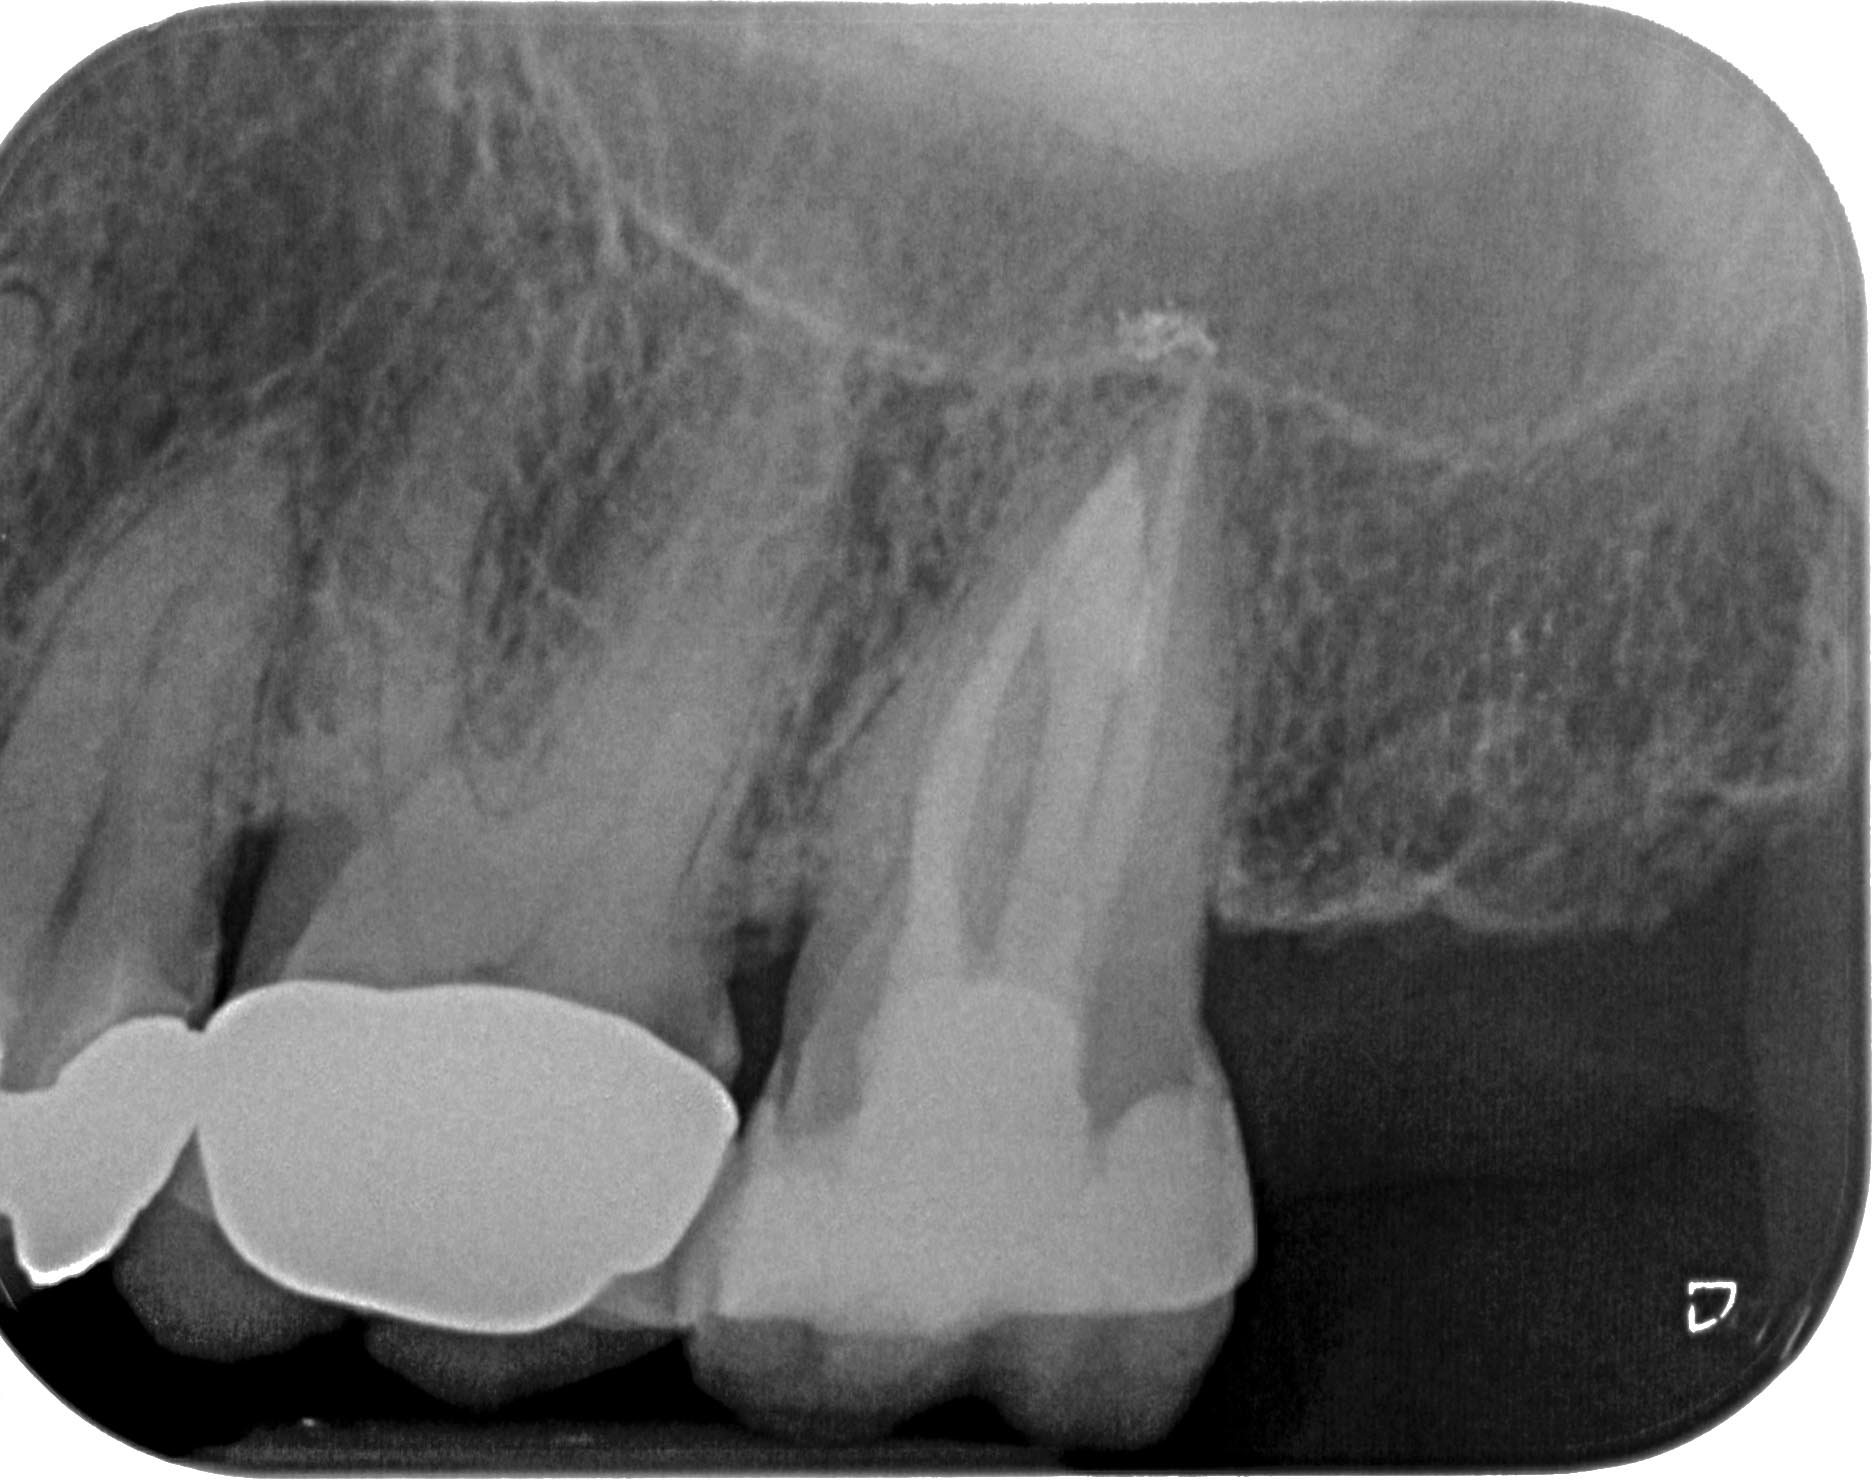

KC27-1-7 Veröffentlicht 25. Juni 2015 am 1874 × 1483 in Zahn 27- Interne Resorption, apikale Aufhellung